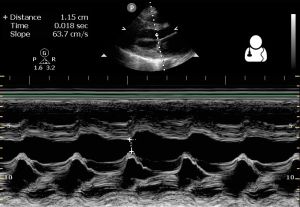

- Echocardiography

- bedside TTE can show LV dilation and LV systolic dysfunction